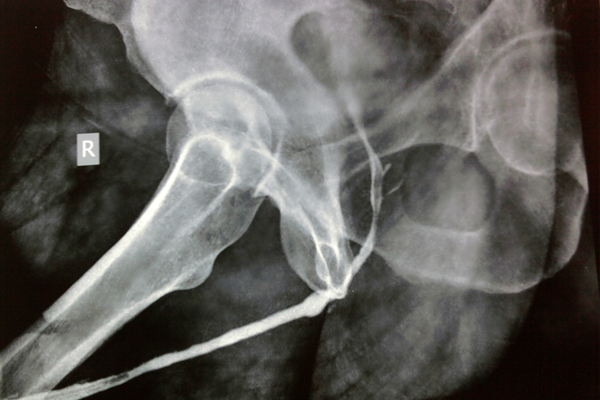

Mr Amarjeet singh (name changed) 19 yr young boy employed in shipping company. He was trapped between metallic door in submarine and sustained crush fracture of pelvis. He developed retention of urine with urethral bleeding. Underwent emergency surgery for pelvic brim (pelvic girdle) fixation and suprapubic catheterisation. He was not able to pass urine through urethra because of complete disruption at the level of prostatomembranous urethra. He approached me and then after evaluation, the diagnosis of PFUDD (pelvic fracture urethral distraction defect) was made. He underwent successful urethroplasty.